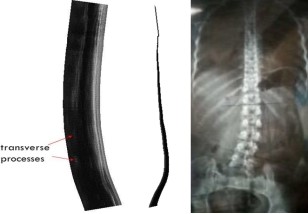

◆ 更重要的是,本人提出了一个全新的超声宽景成像概念-即2.5D EFOV (又称曲面宽景成像)。如图13所示,探头的扫描轨迹不再局限于2D平面内,而是可以是任意轨迹(一条曲线),由此可以构建曲面宽景图。该方法摈弃了图像配准算法,采用更精确的空间定位传感器,相比传统2D EFOV技术,2.5D EFOV的成像准确性大大提高,可以在临床上精确的测量组织的几何参数。

◆ 我们发现,2.5D EFOV更适合扫查人体脊柱。目前,对脊柱侧弯的医学成像方法主要是X光片和CT,这会对患者造成辐射损伤;尤其是青少年脊柱侧弯病人,正在生长发育阶段,而脊柱矫正治疗需要病人频繁接受X光扫描,以确定脊柱矫正的程度,对病人的身体造成极大伤害。经过与中山大学附属第一医院脊柱外科的杨军林教授(国内脊柱侧弯诊断与治疗领域的权威专家)多次交流,我们已经开展了利用2.5D EFOV扫查脊柱侧弯病人的实验,目前已经测试了30多例,取得了较好的效果,测量误差与X光片的测量结果相比仅为1%-2%。该项成果获国际医学成像领域顶级期刊IEEE Trans Med Imaging录用,已在线发表。

◆ 本人指导研究生开发实现的2.5D EFOV技术获2013年度广东省大学生“挑战杯”特等奖。目前,我们与珠海和佳医疗设备有限公司合作完成了技术产品定型(由伍钟巍总工负责),一台样机正在中山大学附属第一医院康复医学科进行临床测试(由李乐副研究员负责)。杨军林教授认为:我们的技术不仅可以测量Cobb角,还可以测量脊柱椎盘的旋转角度,比现有的X光片更好,必将在脊柱侧弯康复预后领域有着极好的应用前景和广阔的市场空间。

图13.本人提出的2.5D EFOV成像原理(左)与肌骨组织成像图(右)。

图14.本人提出的2.5D EFOV成像应用于某女性脊柱侧弯病人。左:2.5D EFOV结果图;右:X光片成像图。通过测量Cobb角进行对比,两者误差仅为1%-2%,表明2.5D EFOV的成像准确性已满足实际临床检查的需要。